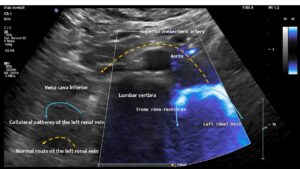

These images, taken from the front of the patient, show the tronc réno-rachidièn. This vessel runs in a U-turn along the left side of the lumbar spine towards the back, entering the intervertebral foramen and thus putting pressure on the spinal canal. They demonstrate that the preaortic portion of left renal vein (yellow dashed arrow) does not carry any blood, meaning that all of the left renal venous blood must be diverted via the tronc réno-rachidièn. The other natural collateral pathway, the left ovarian vein, is less significant here. In this patient ( as in many arteries with left renal vein compression) , the collateralisation via the left ovarian vein towards the pelvic venous circulation is obstructed by compression of the left common iliac vein. This combination is very common and requires simultaneous treatment of both the left renal vein and the left common iliac vein in one operation, by shielding both with a PTFE shield.

Blood within the tronc réno-rachidièn is modulated in a pulsatile manner, demonstrating rhythmic compression of the left renal vein between the aorta and superior mesenteric artery. This compression is so pronounced that no blood flow is visible ventral to the aorta only the pressure wave is transmitted towards the collateral vessel.

This image demonstrates the transfer of the pulsatile pressure of the aorta and the superior mesenteric artery towards the tronc réno-rachidièn (yellow arrows). Both arteries completely squeeze the final portion of the left renal vein obstructing the entire blood flow, but the pressure is rhythmically transferred towards the spinal canal and thus the spinal cord. Not rarely affected patients develop headaches and migraines which was not the case in this patient.